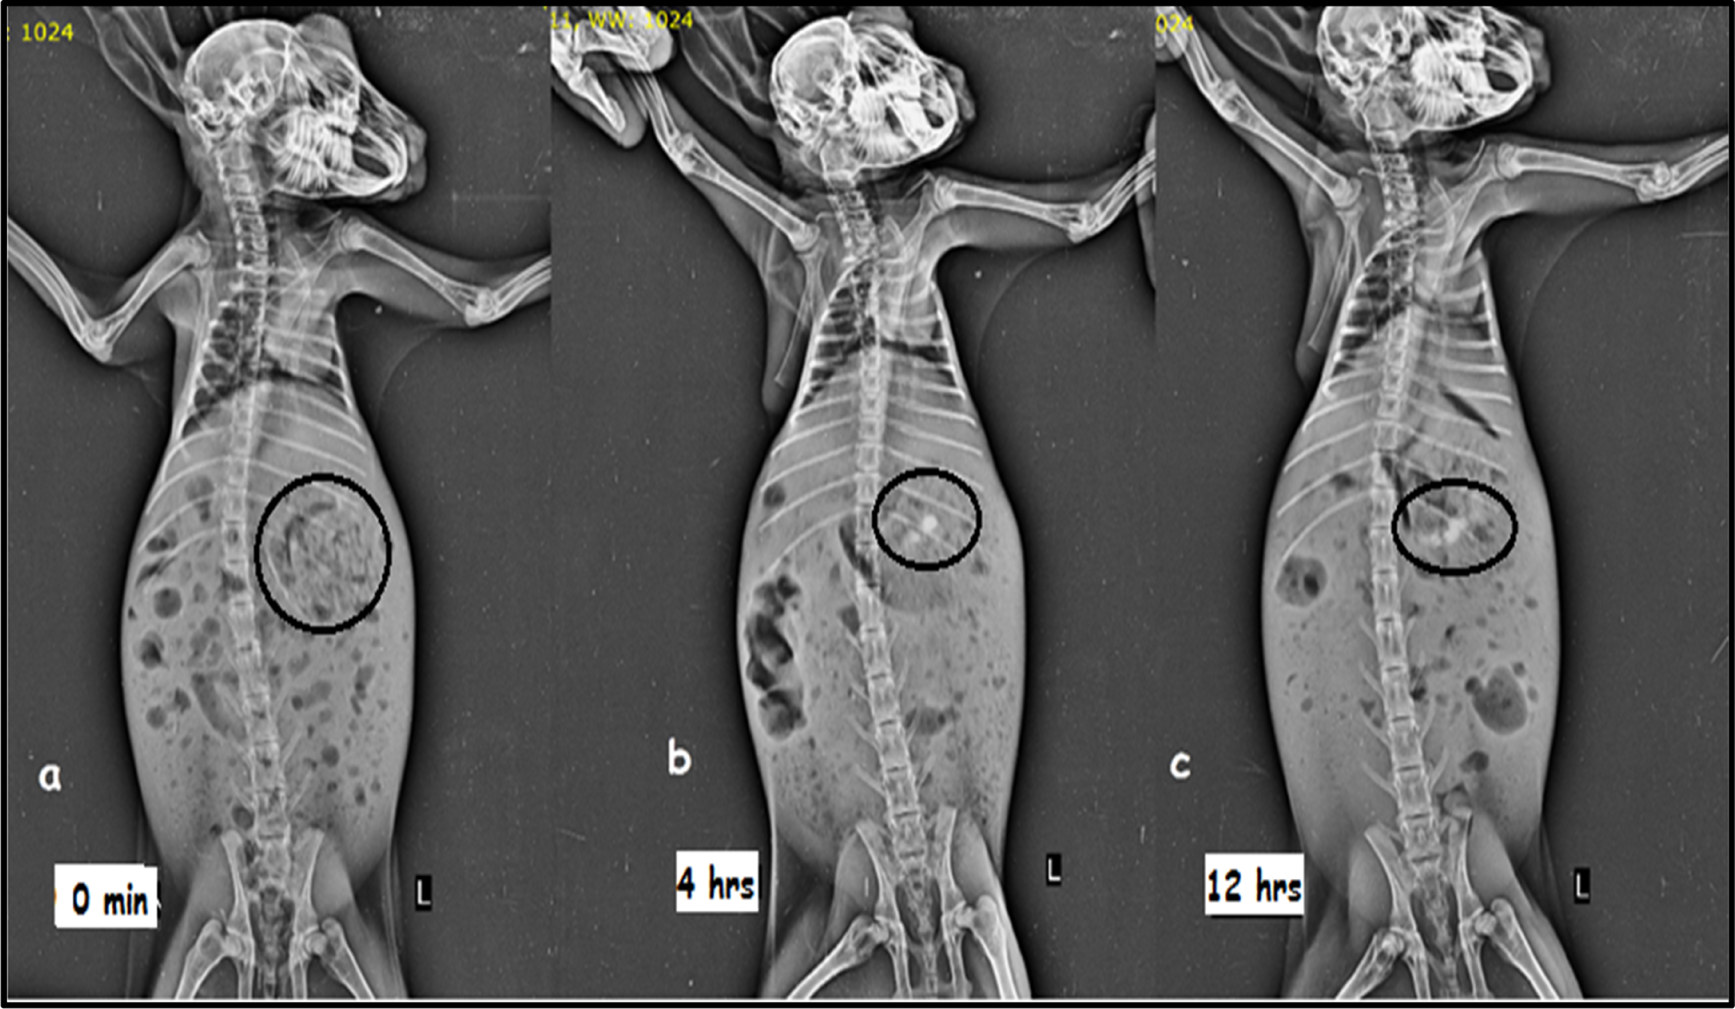

2.6 In vivo radiographic study

The gastroretention capability of the optimized formulation could be verified using different techniques, comprising radiographic investigation, gastroscopy, gamma scintigraphy, magnetic marker monitoring, etc. (Mandal et al., 2016). Also, three fit albino rabbits weighing 2.0 kg–2.2 kg were used for the in vivo radiography experiments. The Institutional Animal Ethical Committee (IAEC) gave its approval to the study’s protocol (BIP/IAEC/2015/05) in accordance with its directives from the Committee for the Purpose of Control and Supervision of Experiments on Animals (CPCSEA). The X-ray opaque material was added to the optimized mixture by switching out the MTG for barium sulfate while leaving all other ingredients the same to create gastroretentive floating matrix tablets (Tadros, 2010). The content of barium sulfate in the optimized formulas was low enough to allow the formulation to float but also sufficient to make it visible by X-ray. The formulation was given to an albino rabbit after an overnight fast in order to conduct an in vivo X-ray imaging study. To check for radio-opaque substances in the stomach, a radiograph was obtained at 0 h, right before the tablet was administered. Water was readily available at the time of study for rabbits, but they were not permitted to consume solid food. The X-ray pictures were taken after 4 h and 12 h to track the presence of optimized floating matrix tablets in the stomach (Shin et al., 2019; Wani et al., 2020; Younis et al., 2020).

3.8 Radiographic study

Figure 5 shows the X-ray images obtained at 0, 4, and 12 h. The pictures evidently show white spots in the stomach, which indicates that the formulation stayed buoyant in the rabbit stomach for 12 h in gastric fluid. Thus, the study supports the floating matrix tablet for MTG’s gastroretentive activity (Patel M et al., 2021; Patel MB et al., 2021).

FIGURE 5

X-ray images showing the presence of barium sulfate-loaded floating matrix tablet in the rabbit’s stomach: (A) 0 min, (B) 4 h, and (C) 12 h.